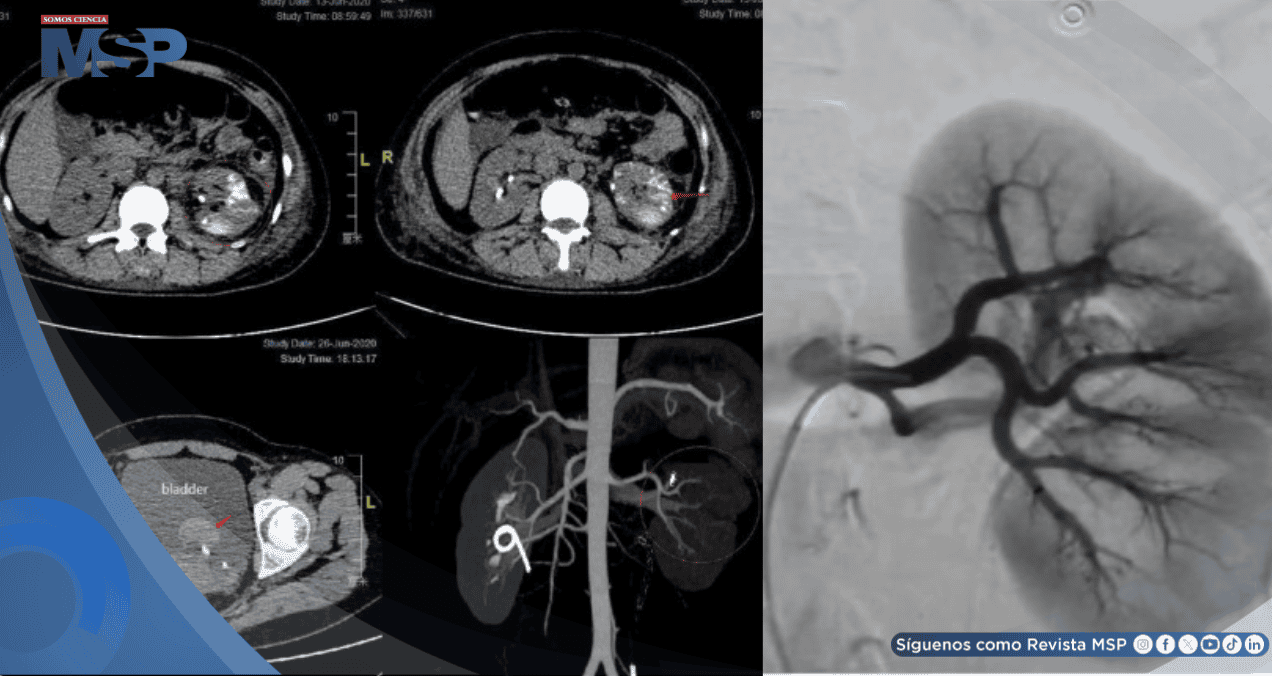

Este hallazgo se confirmó mediante angiografía por sustracción digital (DSA), la cual mostró una arteria renal izquierda dilatada y tortuosa que formaba una masa vascular, con opacificación precoz de la vena renal y la vena cava inferior en la fase arterial.

Se realizó una embolización urgente mediante cateterismo selectivo de la arteria renal izquierda. El procedimiento consistió en la oclusión con partículas de esponja de gelatina (560–710 µm) reforzada con tres resortes helicoidales. La DSA de control confirmó la eliminación exitosa de la derivación arteriovenosa.

Sin embargo, dos días después, una tomografía computarizada (TC) reveló múltiples lesiones de alta densidad en el parénquima renal izquierdo y líquido libre en la cavidad pélvica, indicando sangrado residual. La paciente fue dada de alta al octavo día post-embolización.

Quince días después, la paciente fue rehospitalizada tras presentar hematuria recurrente. El análisis de orina mostró un recuento elevado de glóbulos rojos (45.690/µl). Una nueva TC abdominal evidenció un ligero sangrado en el riñón izquierdo y un hematoma vesical.